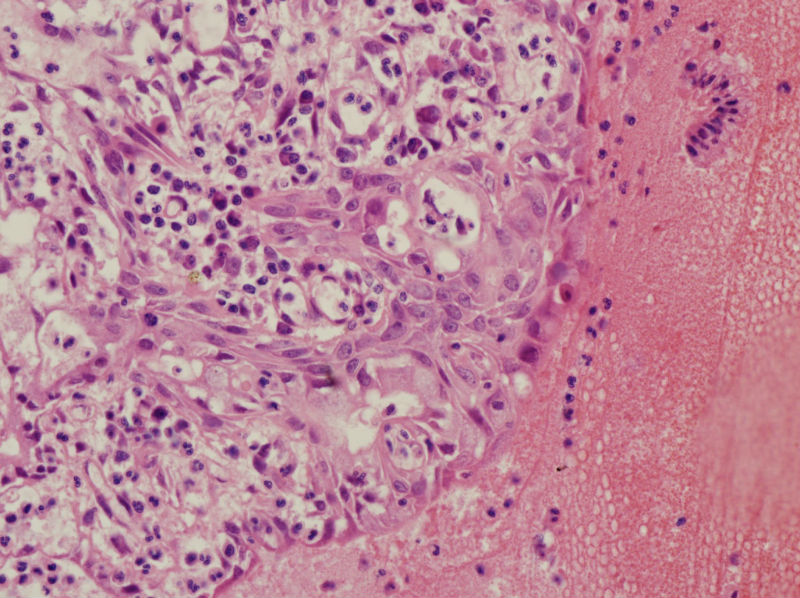

45岁,宫颈息肉?请老师指教

• 45岁,宫颈息肉?请老师指教图1

图1

慢性炎,腺体有鳞化

宫颈及宫颈内膜息肉,腺体增生及鳞化,鳞化跟中药没有关系,跟炎症刺激有关系。

宫颈息肉伴腺体鳞化,微腺体增生

宫颈息肉,伴有微小腺体增生。

宫颈息肉伴腺体的鳞化,我个人感觉息肉的分型比较复杂,有的地方存在宫颈腺体增生型,有些地方血管型,还有纤维型也可见。

宫颈息肉伴鳞化和微腺体增生

宫颈息肉伴糜烂,局部腺体及黏膜上皮鳞状上皮化生。至于说具体分型,与临床治疗和预后都没有关系,可以不分。

Benign endocervical polyp with SM and MGH. You do not need classify benign endocervical polyp because it has no impact on clinical management.